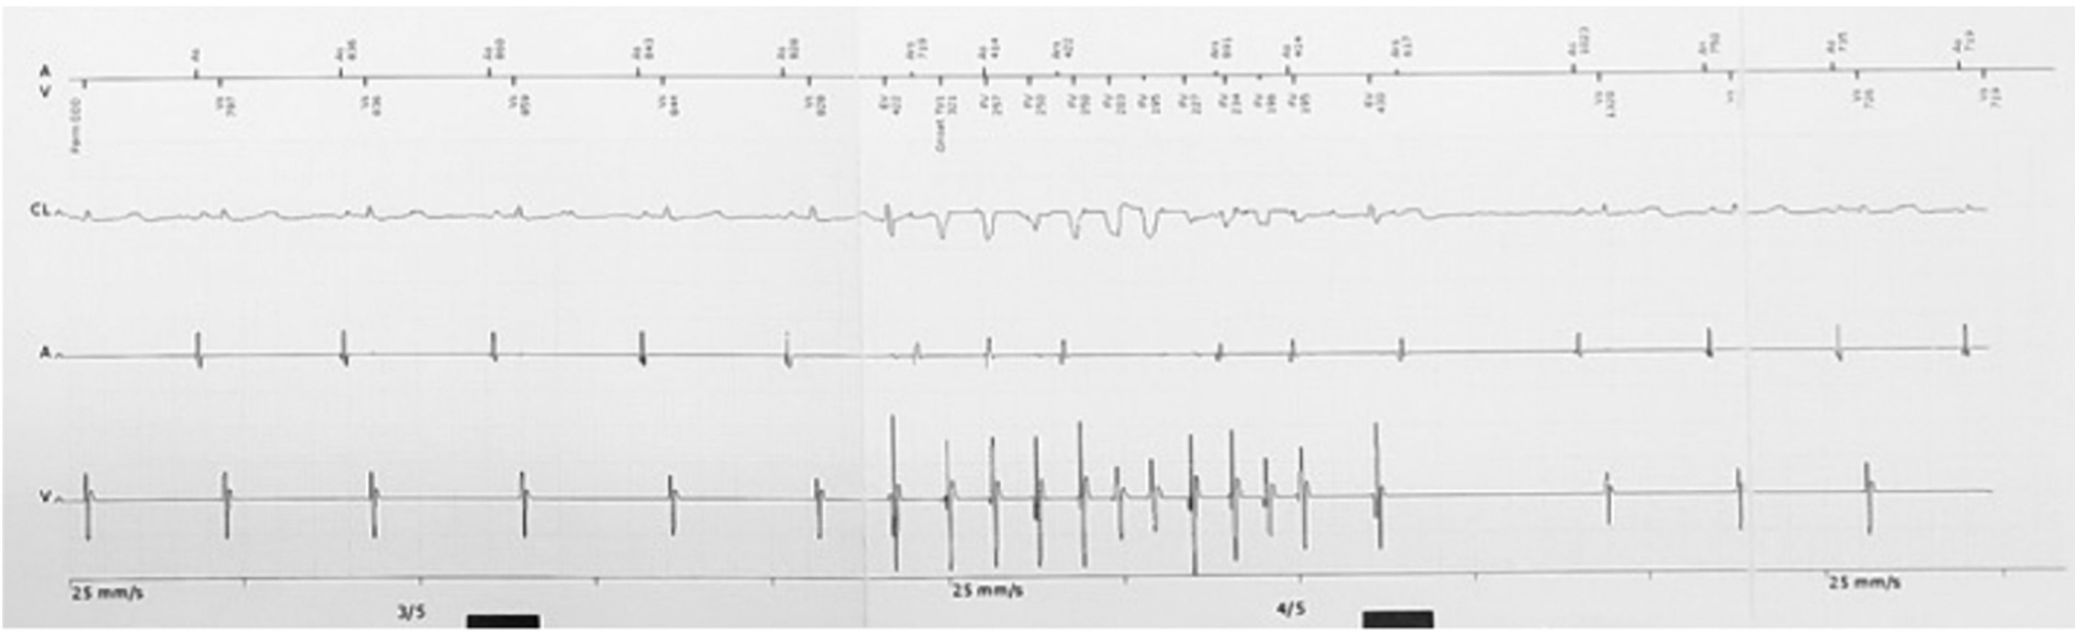

然而,故事并沒有這么簡單,入院后室早才一步步顯露出它的真面目。這次發(fā)作的室早與入院時明顯不同,聯(lián)律間期縮短至300ms,出現(xiàn)在T波頂峰,室早后誘發(fā)了尖端扭轉(zhuǎn)型室速(TdP),室速發(fā)作時患者同時出現(xiàn)了暈厥發(fā)作。此后,患者又出現(xiàn)了多次TdP發(fā)作,且發(fā)作時間越來越長,最終演變成室顫,體外除顫后才恢復正常竇律。

圖3 短聯(lián)律間期室早誘發(fā)尖端扭轉(zhuǎn)型室速